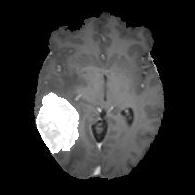

(a) (b) (c) (d) (e)

Comparison to Competing Methods:

We have compared the performance of our model against the most popular deep learning-based semantic segmentation networks, U-Net [9] and V-Net [7] (Fig. 3). Our model outperforms both by a considerable margin in all evaluation metrics. In particular, U-Net performs poorly in most cases due to the high false positive of its segmentation predictions, as well as the imprecision of its boundaries. The powerful residual block in the V-Net architecture seems to alleviate these issues to some extent, but V-Net also fails to produce high-quality boundary predictions. The emphasis of learning useful edge-related information during the training of our network appears to effectively regularize the network such that boundary accuracy is improved.